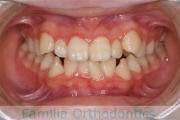

出っ歯・口ぽかんを治したいということで来院されました。小臼歯を抜歯して歯科矯正用アンカースクリューを併用したマルチブラケット法を行いました。約3年半、40回程度の通院が必要でした。前歯の移動量が大きく、その部位の歯根吸収のリスクが高いケースでした。